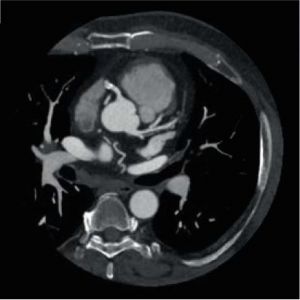

Об'ємна КТ дозволяє сканувати пацієнтів швидко та з високою якістю зображення. Кожне сканування забезпечує неймовірні зображення коронарних артерій без руху з рівномірним посиленням контрасту. У поєднанні зАіСЕ (Advanced intelligent Clear-IQ Engine), технологією Deep Learning Reconstruction, ви завжди отримуєте неперевершенуякість зображення.

Myocardial Perfusion Imaging

Точна ідентифікація уражень, що обмежують кровотік та потребують реваскуляризації, за допомогою візуалізації перфузії міокарда. Отримання об'ємного зображення всього серця за одне обертання при наднизькій дозі за допомогою                Aquilion ONE / GENESIS Edition.